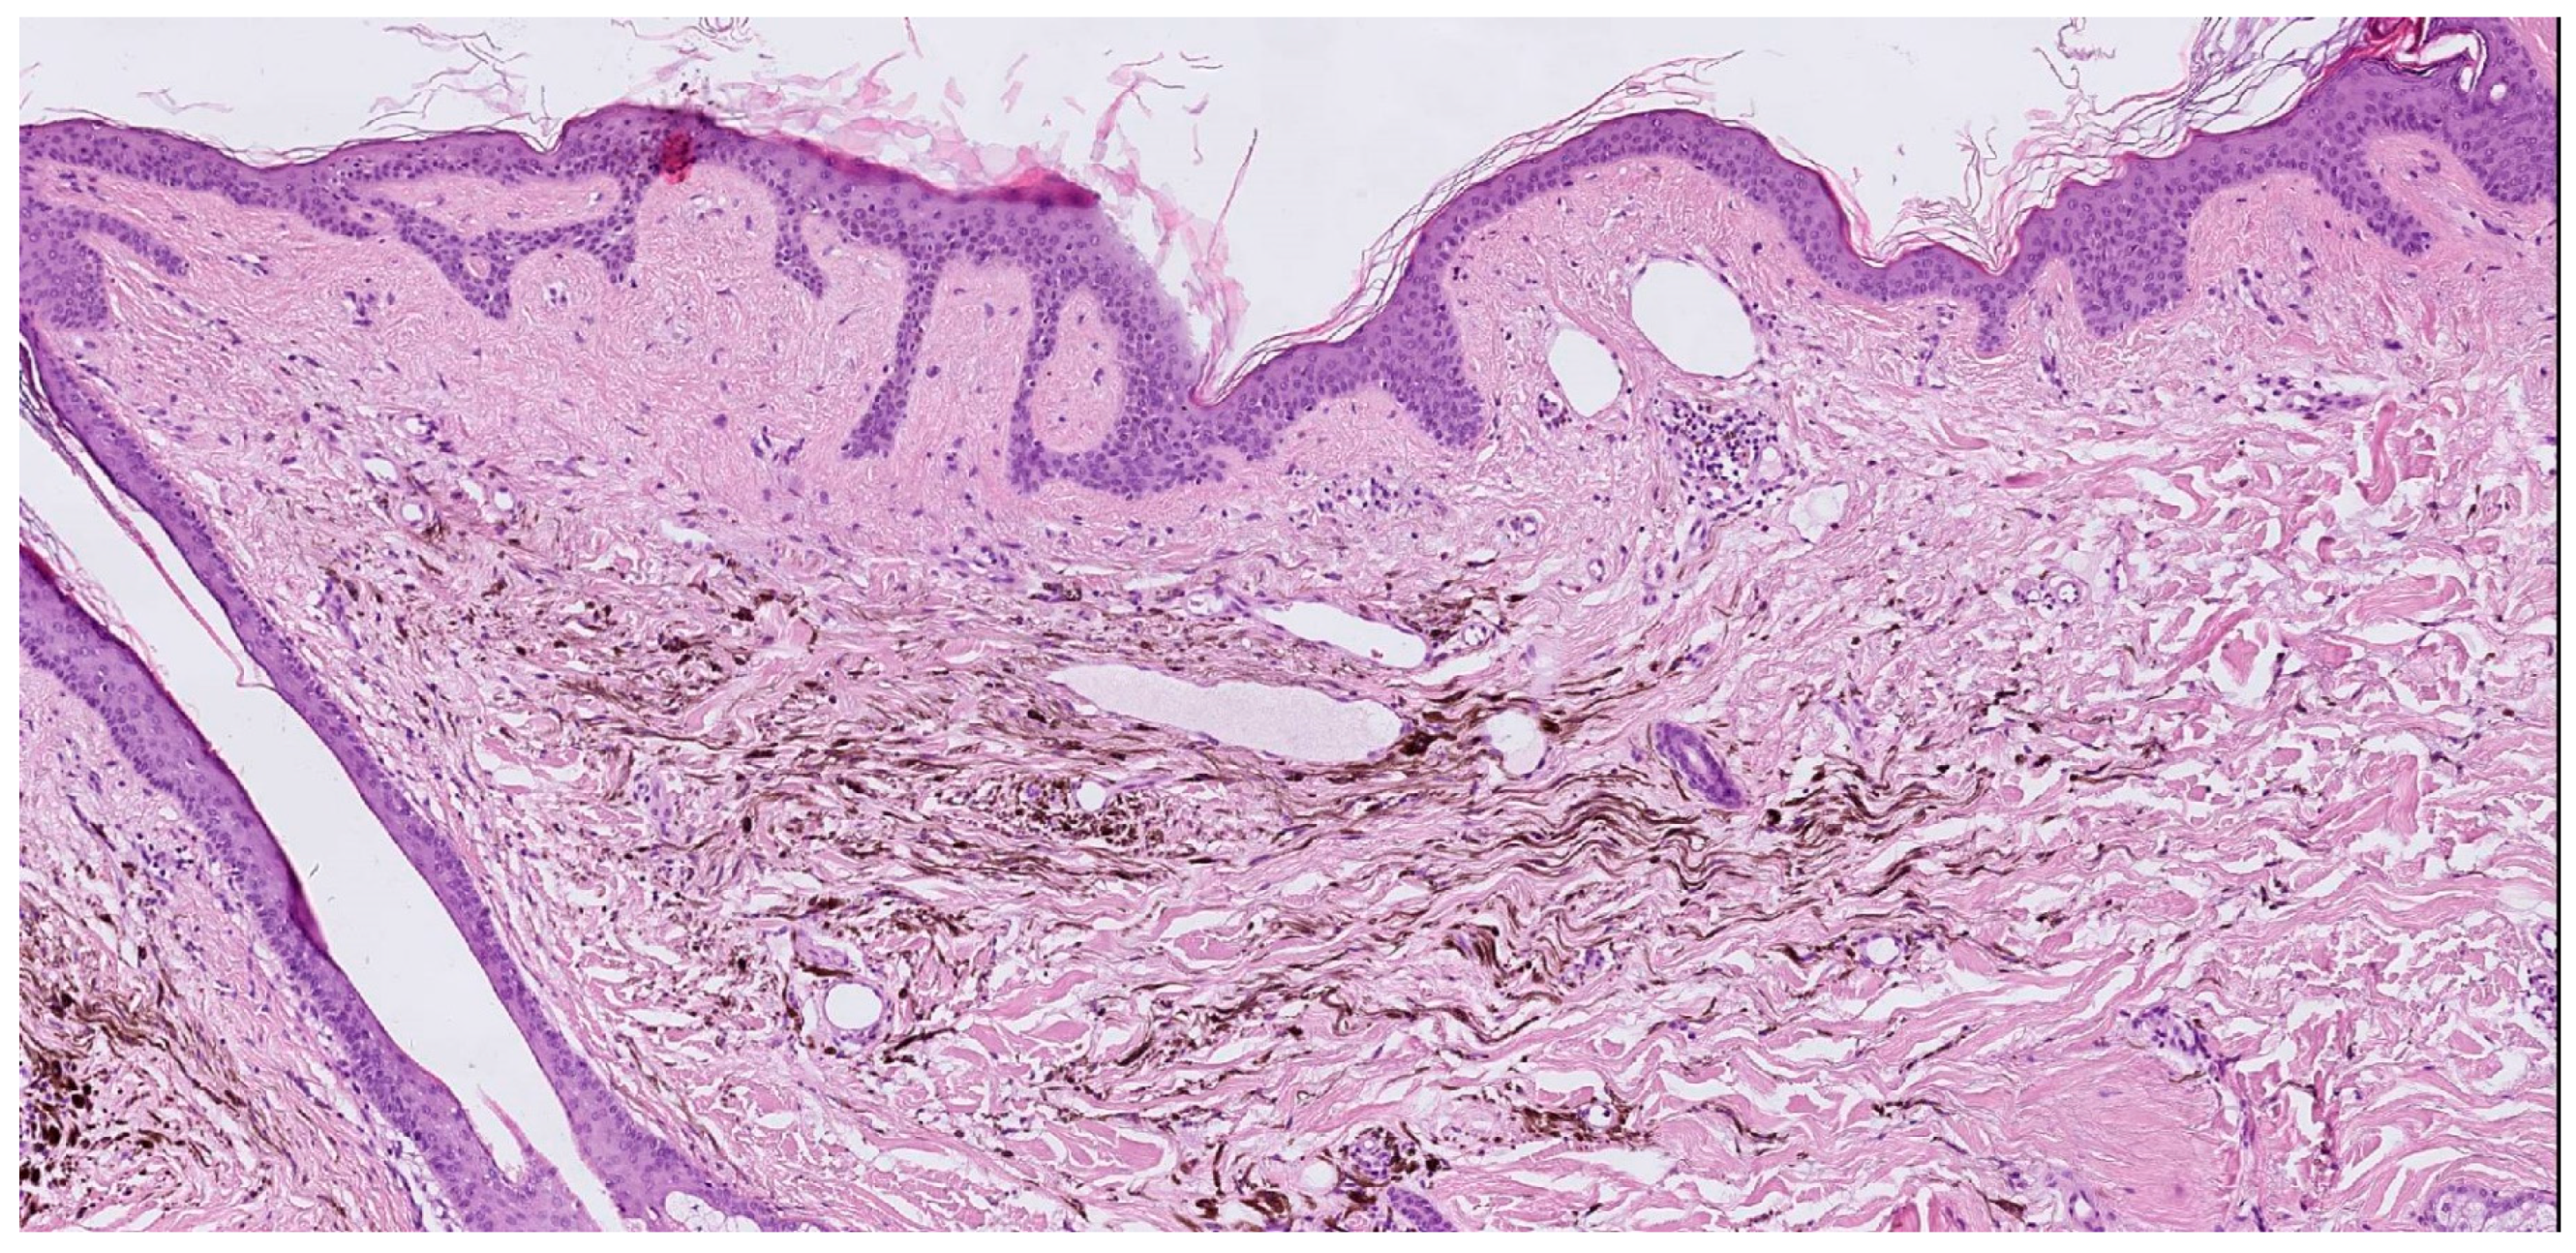

| Case | Age in Years/Gender | Clinical Morphology | Dermoscopic Features | Histology |

|---|---|---|---|---|

| 1 | 53/M | Blue–black plaque with multiple bluish papules and macules | Homogenous blue–gray pattern with yellow hue | Locally advanced melanoma |

| 2 | 86/M | Blue–black plaque with multiple blue satellitosis | Homogenous blue–gray pattern | Metastatic melanoma |

| 3 | 38/F | Blue nodule with agminated pigmentated macules | Homogenous violet-blue pattern with serpentine vessels | Desmoplastic blue nevus |

| 4 | 77/F | Blue–black macule and interspersed pigmentated lesions of scalp | Homogenous blue–brown pattern | Common blue nevus |